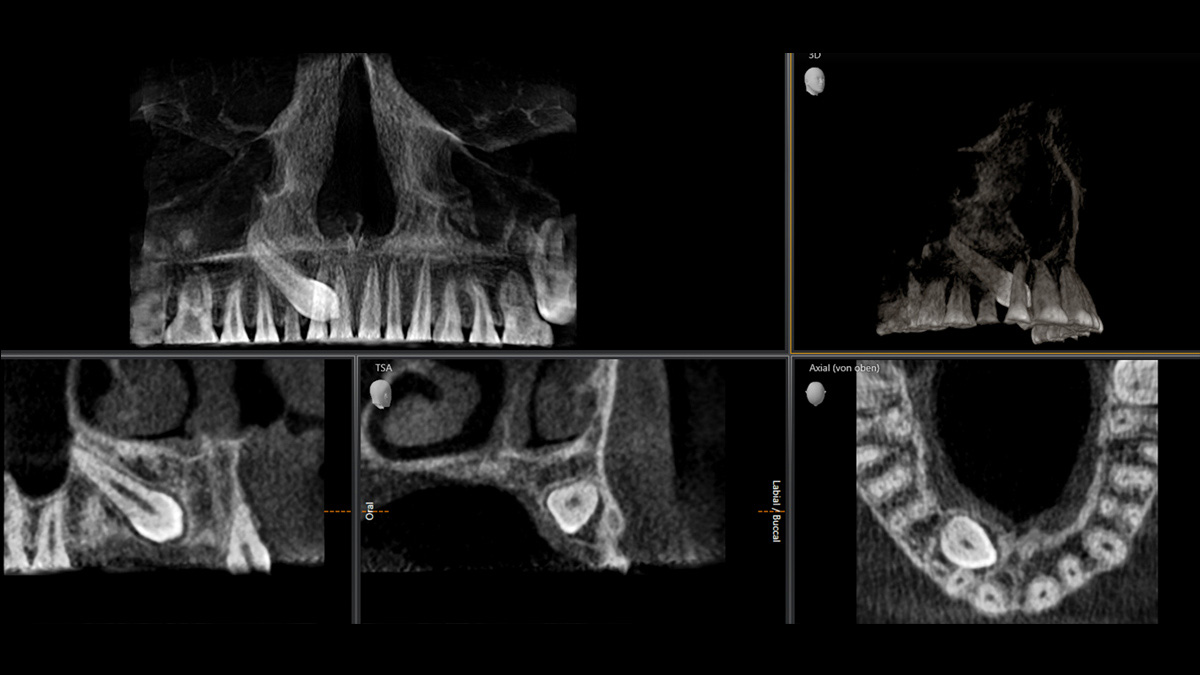

Mit dem Low Dose-Modus erhalten Sie 3D-Bilder im Dosisbereich einer 2D-Röntgenaufnahme. Im HD-Modus werden während eines einzelnen Umlaufs mehr als 800 Einzelbilder aufgenommen und zu einem 3D-Volumen mit bis zu 80 μm zusammengeführt. Der Vorteil für Sie: rauschärmere Aufnahmen in hoher Auflösung

Ø 5 cm x 5,5 cm bis Ø 8 cm x 8 cm (optional Ø 11 cm x 10 cm)

Ein breites Spektrum an Volumengrößen für verschiedene diagnostische und klinische Anforderungen von Ø 5 × 5,5 cm bis Ø 11 × 10 cm